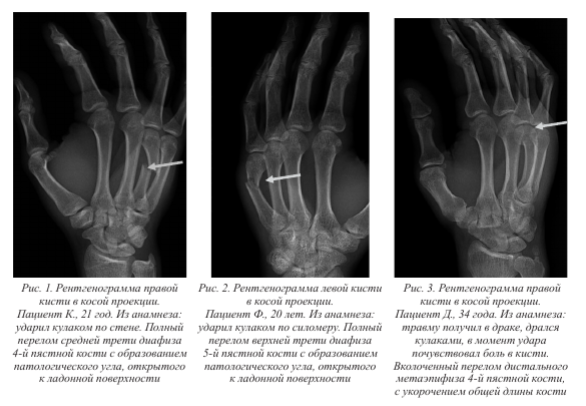

В 8 случаях переломы имели признаки вколоченных, края проксимального и дистального отломков были значительно сближены друг с другом, а также находились в суперпозиции, поэтому достоверно установить зоны сжатия и разрыва костной ткани не представляется возможным. Также формирование вколоченных переломов сопровождалось уменьшением общей длины травмированной кости. В 7 случаях отмечены полные косо-поперечные переломы, в 3 случаях - косо-продольные. Патологический угол перелома может быть открыт как в сторону ладони, так и медиально или латерально. Зона сжатия, как правило, в случаях образования патологического угла находилась на ладонной поверхности кости, а зона растяжения - на тыльной (рис. 1-3).

У одного пациента возник винтообразный перелом диафиза 4-й пястной кости (рис. 4).